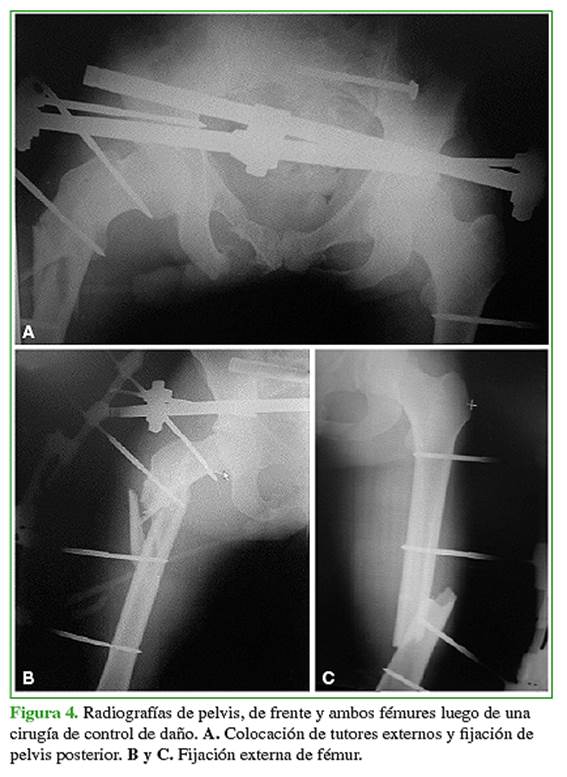

Luego de la revisión primaria y la reanimación inicial según el protocolo ATLS con la estabilización transitoria de la fractura mediante tutores externos, se programó la osteosíntesis (Figuras 3-5).

La fractura de fémur había sido tratada con clavos endomedulares en el 95,7% (n = 22) (Figura 6) y con placa y tornillos solo en el 4,3% (n = 1). La mediana de días de internación de esta población fue de 8 (rango 5-10). La mediana de la duración de los procedimientos fue de 247 min (rango 120-480) y la mediana de la pérdida hemática estimada durante la operación, de 500 ml (rango 300- 900).